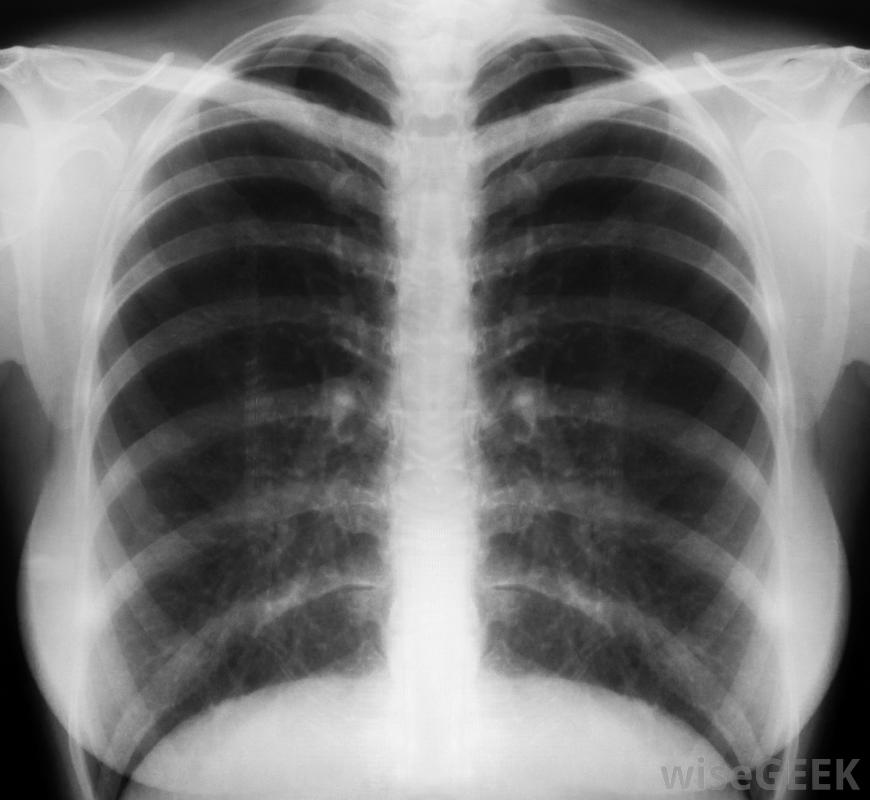

支氣管炎發生在支氣管發炎或發炎時。成人支氣管炎的癥狀通常包括咳嗽、胸痛、疲勞和頭痛。全身酸痛、低燒、流淚和喉嚨痛也可能伴隨支氣管炎。然而,支氣管炎患者,可能有所有或僅有的幾個癥狀。喉嚨痛可能是支氣管炎的征兆。有兩種支氣管炎的類型-急性支氣管炎和慢性支氣管炎。急性支氣管炎是由細菌或病毒引起的大支氣管發炎,通常持續兩到三周。慢性支氣管炎是支氣管炎的持續性炎癥,其特征是反復咳嗽,產生痰和粘液,至少持續三周慢性支氣管炎在吸煙人群中最為常見。胸部x光片對消除肺炎比確認支氣管炎更有效成人急性和慢性支氣管炎的癥狀包括不停的咳嗽,可能產生清、白、綠或黃灰色的痰。其他癥狀包括疲勞和低熱。呼吸急促,喘息和胸痛也可能發生。支氣管炎患者可能只經歷一到兩種癥狀,而不是所有癥狀除了這些癥狀外,慢性支氣管炎患者還可能出現持續咳嗽,這種咳嗽通常在早晨或潮濕的天氣更為嚴重,粘液產生,個體呼吸困難。成人支氣管炎的治療有助于緩解癥狀。推薦的治療方法通常包括多喝水,充分休息,戒煙并服用阿司匹林、對乙酰氨基酚或布洛芬,以降低發熱和減輕疼痛。從加濕器或熱水淋浴中呼吸蒸汽可以幫助咳嗽更有效,非處方的止咳藥可以幫助停止咳嗽,讓患者入睡。含有愈創木酚的祛痰止咳藥有助于緩解咳嗽,使其更有效,并有助于排出體內的粘液。醫生可以開處方藥,如抗生素或處方強效咳嗽藥。成人支氣管炎可能會出現輕微的發燒、疲勞和胸痛。醫生通過評估患者的癥狀并用聽診器聽他們的胸部來診斷成人支氣管炎。在某些情況下,醫生可能會要求咳出的粘液樣本要做細菌檢查x光片通常用來排除肺炎,而不是確診支氣管炎。喘息和疲勞是支氣管炎的常見癥狀兒童支氣管炎癥狀與成人支氣管炎癥狀相同,非藥物治療也相同,但藥物治療不同,不建議給4歲以下兒童服用任何類型的非處方咳嗽藥,除非兒科醫生建議,否則反復咳嗽是支氣管炎的常見癥狀src="1234562"/>棕色痰可能是慢性支氣管炎的征兆。醫生通過評估患者的癥狀并用聽診器聽他們的胸部來診斷成人支氣管炎患有支氣管炎的患者可能會出現胸痛。